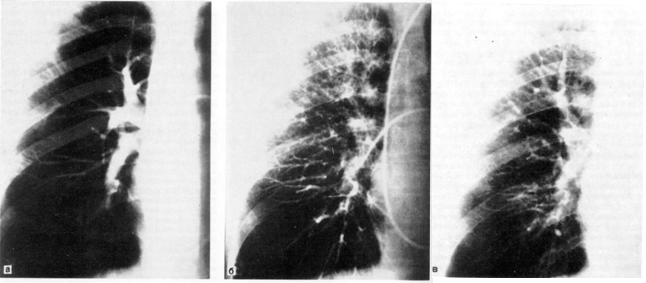

Структура Трахеобронхиального Дерева